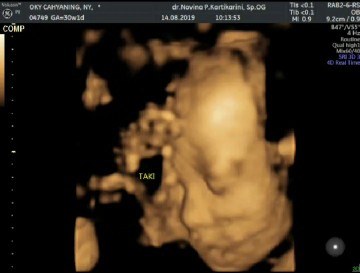

Baby pas 29 week bun๐ skrg udh 32 week . pingin usg 4D lagii๐๐